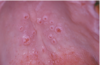

What is this infectious disease?

Oral Verruca Vulgaris

HPV 2,4,6

Also “finger‐like

projections”

remember it’s contagious